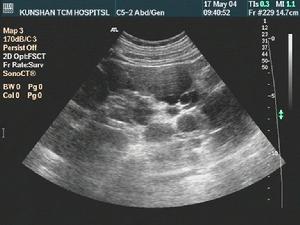

3、B超 藥物所致的急性間質性腎炎B超常顯示雙腎體積對稱性增大。